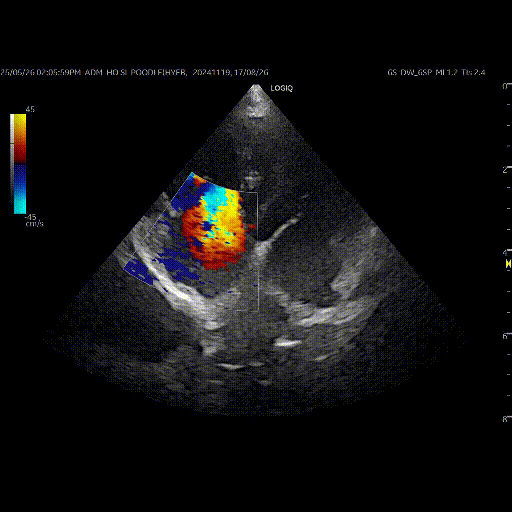

폐동맥 고혈압의 정도와 단계에 대한 평가는 주로 심장 초음파 검사를 진행합니다.

폐동맥에서 우심실 쪽으로 발생하는 역류 여부, 우심실에서 우심방으로 역류되는 혈류 등의 평가를 통해 폐동맥 고혈압의 단계를 추정하게 됩니다.